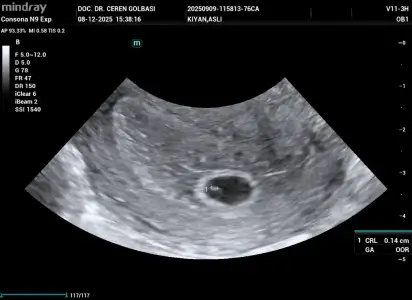

Bugün doktora gittim son adet tarihim 26 ekimdi bebeği göremedik 5+4 olarak söyledi şu anki durumumu benimle aynı olan var mı acaba birde kistim varmış çok ağrı yapıyor kist geçer değil mi

• _QRCodeSendTask_20251208154216_QR_1_202512081538090102OB.webp

_QRCodeSendTask_20251208154216_QR_1_202512081538090102OB.webp

36,2 KB · Görüntüleme: 3